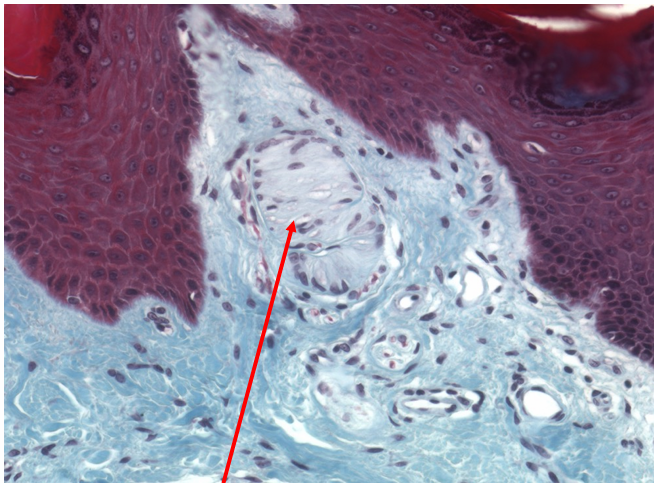

what’s this?

pacinian corpuscle (location of sensory dendrites of afferent neuron)

Meissner’s corpuscle (where sensory dendrites are located)